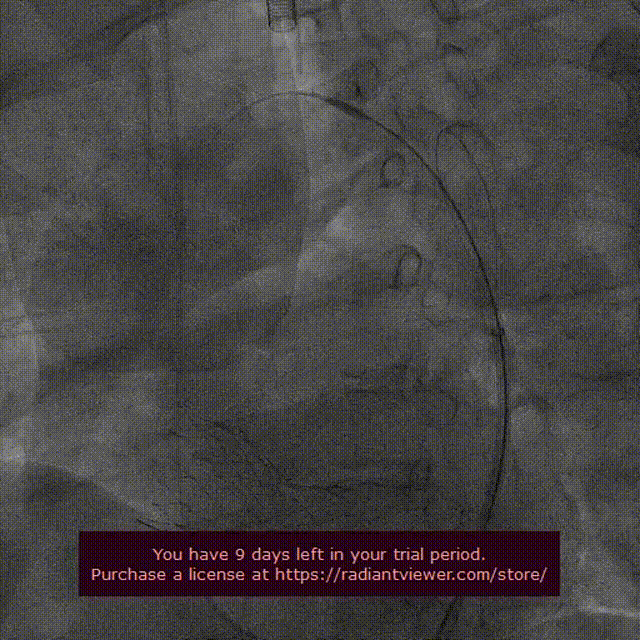

综合考虑瓣环直径、左室流出道直径、钙化分布等因素,彭小平主任团队顺利为患者植入一枚VenusA-Valve®L26型号的人工主动脉瓣膜,借助Snare,克服了超大横位心等难题,血流动力学效果非常好。

Snare辅助跨瓣

VenusA-Valve®完成释放